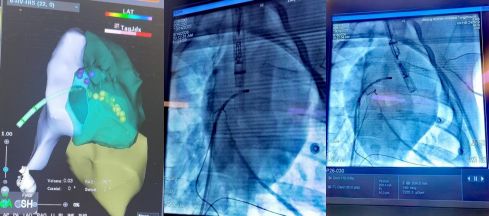

動物實驗選用中型體重的豬,導管由穿刺頸靜脈至上腔靜脈進入心臟,無需動刀。建立入路后,先在心腔內(nèi)超聲指導下,完成心臟內(nèi)部結(jié)構(gòu)的電學重構(gòu),標記出希氏束、左右束支等心臟傳導束的位置,走行路線,以希氏束導管為路標,指導無導線起搏器的植入。無導線起搏器到位后,由心腔內(nèi)超聲成像確認起搏器固定于心臟間隔,測試起搏參數(shù)。

圖4.先建立心腔內(nèi)電解剖結(jié)構(gòu),標記心臟傳導束位置,以電極導管為路標,指導植入無導線起搏器。

通過心臟傳導束起搏,實現(xiàn)左、右心房同步,左、右心室同步、房室順序激動的全生理性起搏方式,是目前起搏治療領(lǐng)域追求的理想目標。全生理性起搏可以避免心臟永久起搏導致的心房顫動、心力衰竭等并發(fā)癥。